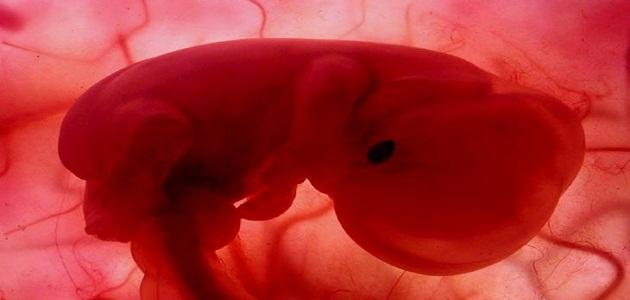

قال تعالى: ﴿ يَا أَيُّهَا النَّاسُ إِنْ كُنْتُمْ فِي رَيْبٍ مِنَ الْبَعْثِ فَإِنَّا خَلَقْنَاكُمْ مِنْ تُرَابٍ ثُمَّ مِنْ نُطْفَةٍ ثُمَّ مِنْ عَلَقَةٍ ثُمَّ مِنْ مُضْغَةٍ مُخَلَّقَةٍ وَغَيْرِ مُخَلَّقَةٍ لِنُبَيِّنَ لَكُمْ وَنُقِرُّ فِي الْأَرْحَامِ مَا نَشَاءُ إِلَى أَجَلٍ مُسَمًّى﴾. أصل خلق الإنسان هو التراب؛ حيث خلق الله تعالى منه سيّدنا آدم عليه السلام، ثمّ خُلِقتْ حواء من ضلع سيّدنا آدم، وبعد ذلك خلقت جميع الأجناس منها عن طريق التناسل، وفي هذا المقال سوف نستعرض أعزّائي القراء كيفيّة خلق الله لسيّدنا آدم، ومراحل الحمل الأولى.

تُلقّح البويضات في المرأة بعد عمليّة التزواج، فتبدأ بعض التغيّرات (التحام النطفة داخل جدار البويضة ثم تتحوّل البويضة إلى المضغة)، فيتشكّل في النهاية الجنين ويبدأ في النمو في رحمها حتى تتمّ عملية الولادة بعد فترة 9 شهور. تعدّ هذه المراحل من أهم المراحل الأولى والتي تُقدّر بنحو اثني عشر أسبوعاً من الحمل حتّى يكون نمو الجنين سليماً وكاملاً ومن دون أيّة مشاكل صحيّة. في بدايات التلقيح تشعر الأم بأعراض معيّنة.